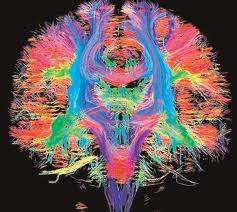

These same "traffic jams" can be seen in the brain on a type of MRI called Diffusion Tensor Imaging, or DTI. DTI measures the movement of fluid throughout the brain, and since water is produced as a byproduct of normal neuronal metabolism we essentially see a "road map" of the brain.

The image below shows the intricate pathways of the brain on a DTI study. The colors are populated by a computer program and represent the direction of fluid flow.

Diffusion tensor imaging does an excellent job of confirming the clinical diagnosis of TBI, and at Ethos it is often paired with susceptibility weighted imaging (SWI) and Neuroquant. It is important to remember that there is not any single test that stands alone to diagnosis TBI, but rather all the tests must be evaluated together. Diagnostics confirm the diagnosis already made by a clinician of brain injury, and help guide therapy and treatment for each patient.